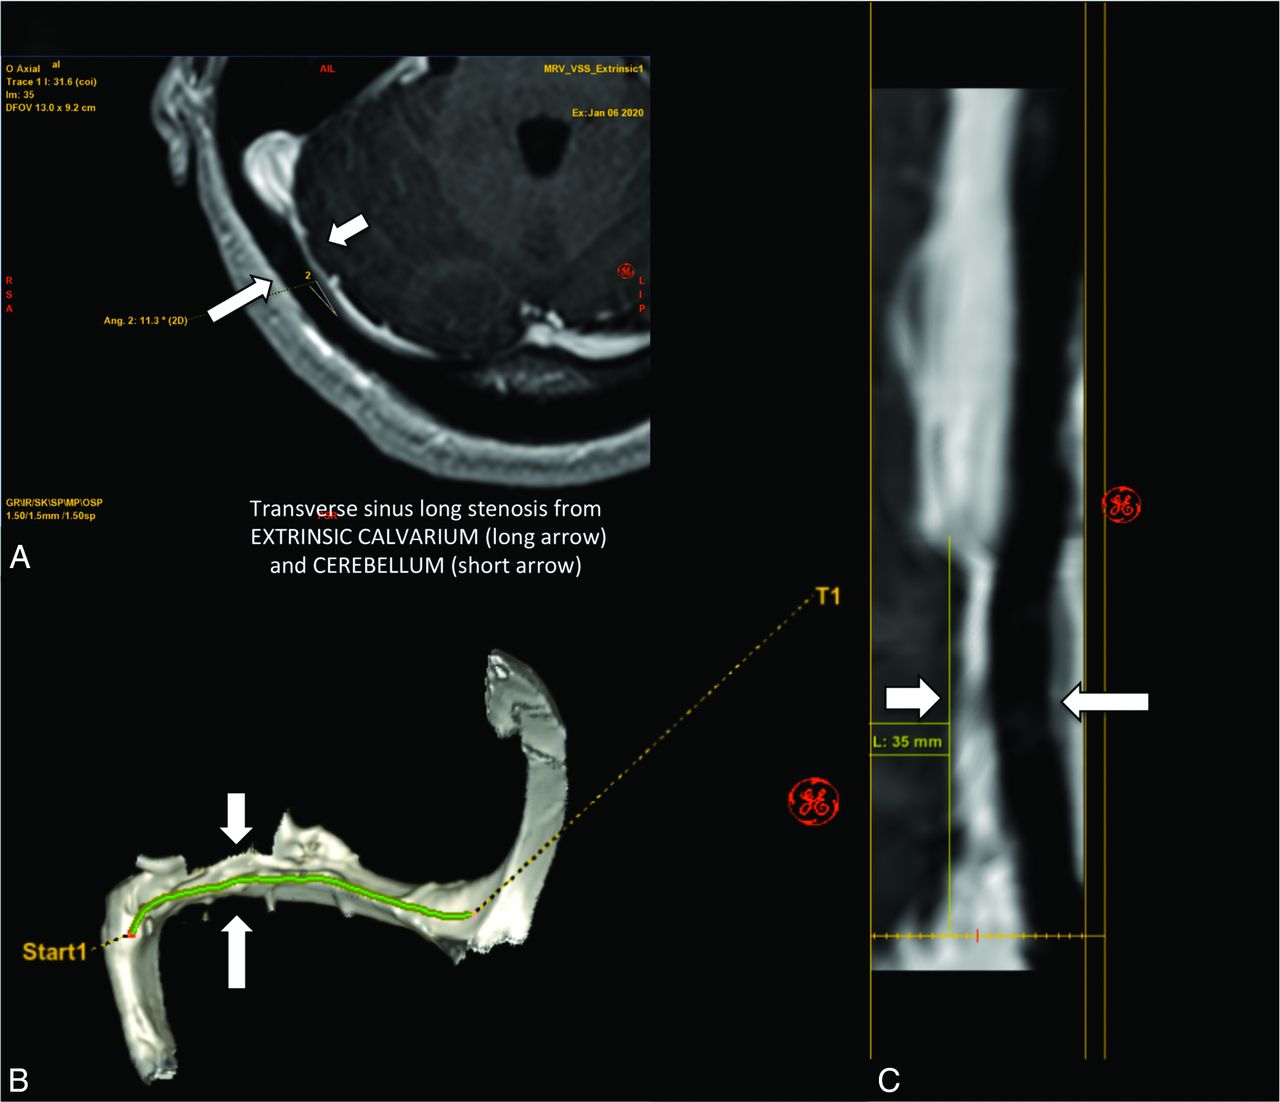

MR images showing extrinsic stenosis of the right transverse sinus. The short arrows point to right cerebellar parenchyma location, and the long arrows points to the occipital calvaria location. A, An axial contrast-enhanced MRV image. B, A 3D reconstruction image. C, A straight-vessel reformat of the right transverse-to-proximal sigmoid sinus from source contrast-enhanced axial images.

MR images showing intrinsic stenosis of the right transverse sinus. The short arrow points to a prominent arachnoid granulation situated inside the sinus. A, An axial contrast-enhanced MRV image, B, A 3D reconstruction image. C, A straight-vessel reformat of the right transverse-to-proximal sigmoid sinus from source contrast-enhanced axial images, noting orange shading of the arachnoid granulation and transparency of the remaining dural venous sinus.